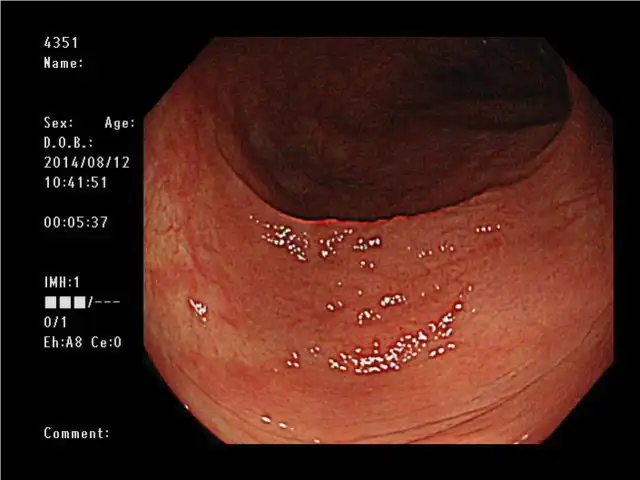

高清 和 NBI(窄带成像)

凭借其高清图像质量,PCF-H290ZL/I使粘膜表面清晰可见。与更明亮的NBI相结合,可增强粘膜组织和毛细血管网络,以进一步支持详细观察。

白光 NBI